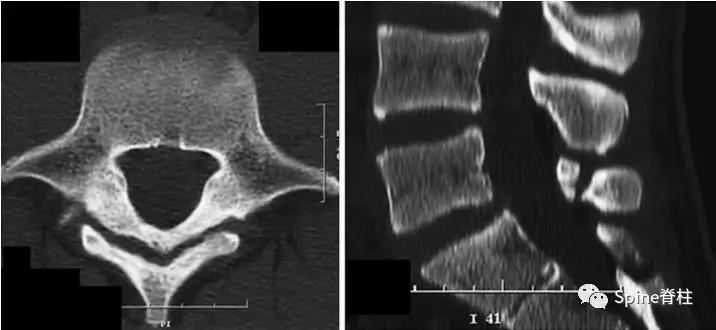

图:起始CT提示L5左侧峡部裂(双箭头),起始CT检查后2个月复查可见出现右侧椎弓根裂(单箭头),4个月复查可见椎弓根裂愈合(单箭头)